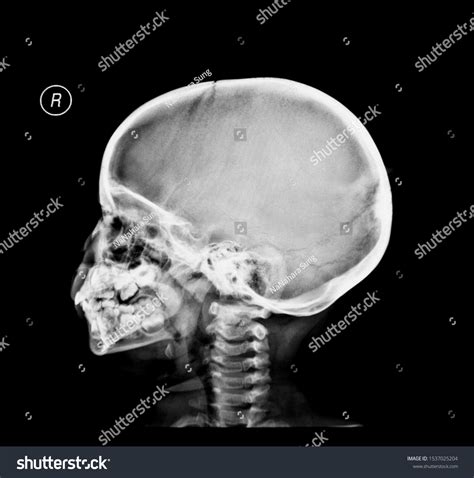

A Baby Skull Xray is a radiographic imaging technique used to visualize the bones of a baby's skull. This non-invasive procedure is essential for diagnosing various conditions, including fractures, deformities, and developmental abnormalities. The X-ray images provide a detailed view of the skull's structure, helping healthcare providers make informed decisions about treatment and care.

Interpreting Baby Skull Xray results requires a trained eye and a deep understanding of pediatric anatomy. Here are some key points to consider:

• Bone Density: The density of the bones can indicate the presence of fractures or other abnormalities.

• Skull Shape: The shape of the skull can provide insights into developmental issues or deformities.

• Fontanelles: The soft spots on a baby’s skull, known as fontanelles, should be checked for proper closure and any signs of swelling or bulging.

• Sutures: The sutures, or the fibrous joints between the skull bones, should be examined for any signs of premature fusion or separation.

Several common findings can be identified through a Baby Skull Xray. Understanding these findings is essential for accurate diagnosis and treatment:

• Fractures: Visible cracks or breaks in the skull bones.

• Deformities: Abnormal shapes or structures of the skull.

• Infections: Signs of infection, such as bone erosion or swelling.

• Tumors: Abnormal growths or masses within the skull.

• Developmental Abnormalities: Issues with the development of the skull, such as premature fusion of sutures.